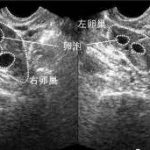

在进行三代试管助孕手术时,需要先对女性进行排卵诱导治疗,并抽取卵子进行体外受精操作。随后将受精卵移植到女性体内,整个过程都需要专业医生的操作和监护。因此三代试管技术的费用主要包括以下几个方面:药物治疗费、手术费、实验室检查费、麻醉费和住院费等。